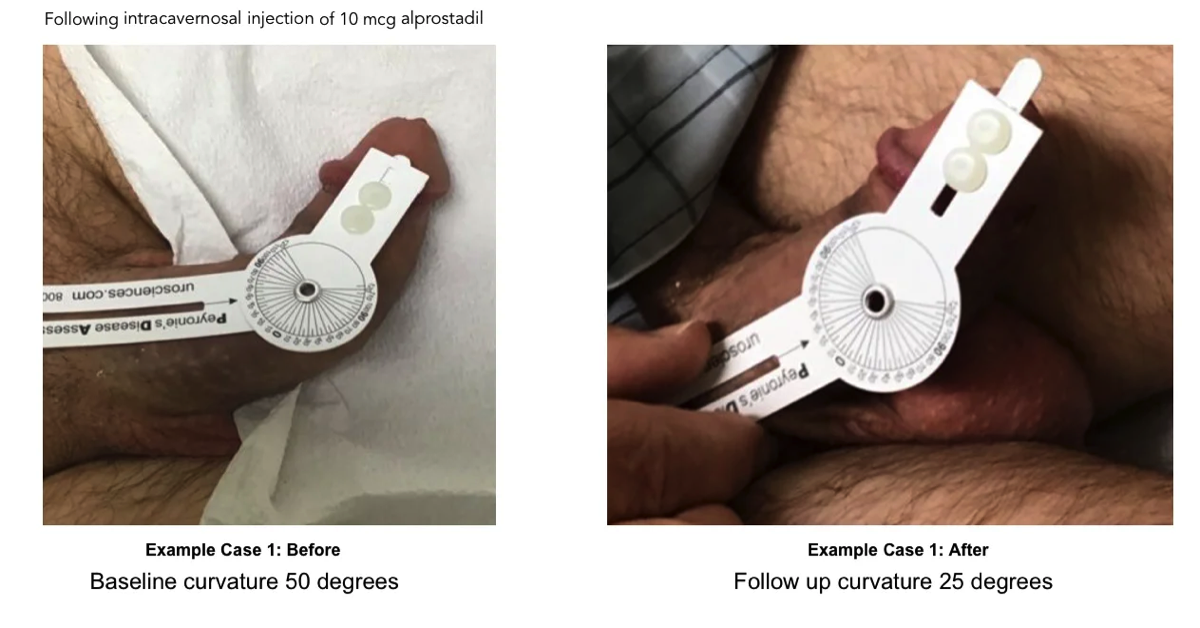

Degree of penile curvature was recorded during the initial and follow up duplex doppler ultrasound by use of a protractor. In many cases, but not all, pictures were provided with protractor showing measurement of current curve. Value of curve was accepted with or without confirmation picture.

Each duplex doppler ultrasound included an intra-cavernosal injection of 10 mcg alprostadil (Nehra, et al., 2015) administered prior to any measurements (Cavallini, Scroppo, & Zucchi, 2016). PSV was recorded every five minutes for a total of thirty minutes on both the left and right sides. For purposes of evaluation, PSV readings less than 30 were considered deficient (Gomez Varela, Mateos Yeguas, Rodriguez, & Duran Vila, 2020) and recorded as “arterial insufficiency”. EDV was also recorded in the same increments. It is commonly recognized that the EDV must be low to offer an effective veno-occlusive mechanism (Cavallini, Scroppo, & Zucchi, 2016). For evaluation, we considered readings >4 cm/sec as insufficient and this is labeled as “venous leak”. A simple ratio calculation of PSV / EDV provided the ratio between the two ratings.

Before and After Peyronie's Treatment Photos

Have you ever Googled "before and after Peyronie's treatment photos"? The only images you'll find are gut wrenching photos taken midway through plication or "incision & graft" Peyronie's surgery.

Following are baseline and follow up images of Peyronie's patients following treatments with ExoSurge®. We hope to share many more soon. Unfortunately, patients must grant us permission to release these photographs, and few are willing to do that.